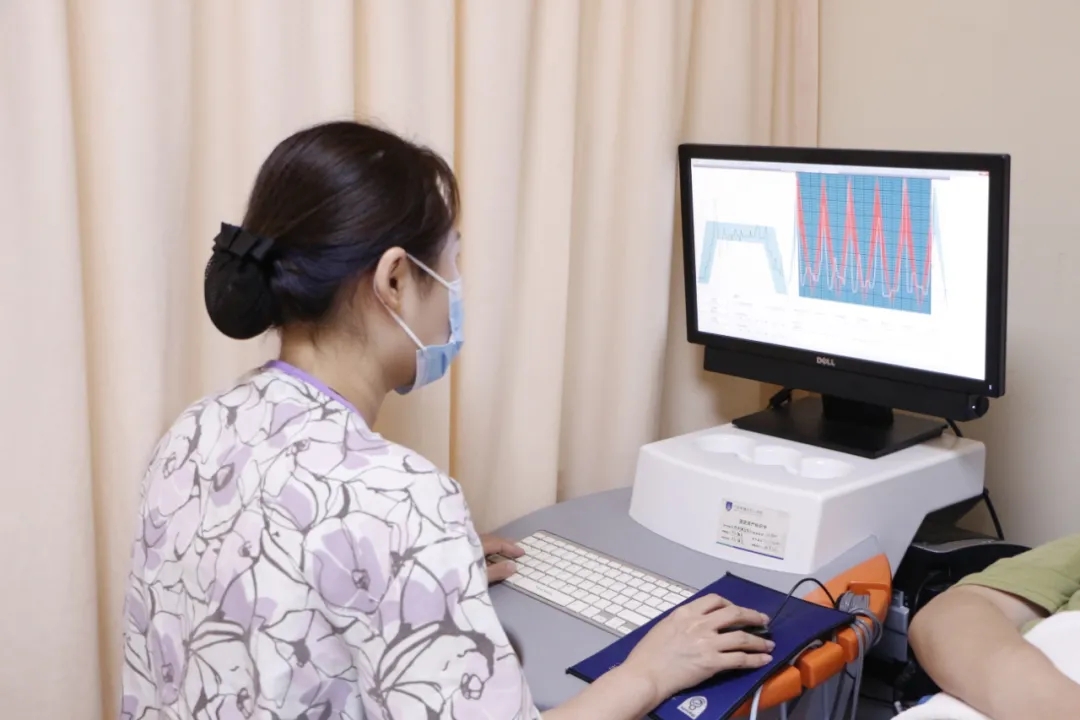

盆底状况评估

接下来就是盆底评估啦,这是很重要的一项!也是产后恢复的必修课!

产后42天恰恰也是盆底肌修复的黄金时期,想修复受损的盆底肌就得先清楚盆底肌的损伤程度,再进行盆底评估。

检查过程中,妈妈们需要放松肌肉,根据仪器做收缩用力。屏幕上有曲线,代表你的肌力,而且美琳达采用的是海龙马和伟思康复治疗仪,这些治疗仪已广泛应用于国内三甲医院,治疗方式是游戏性质的,不会有丝毫的紧张和害怕,像玩游戏一样就结束了,甚至还有妈妈调侃“就这么眼睁睁的看着我的鸟摔死了”。

整个过程下来很轻松,只要根据护士小姐姐的口令就可以了,全程化的数字跟踪,会准确的判断出自己的盆底损伤程度。